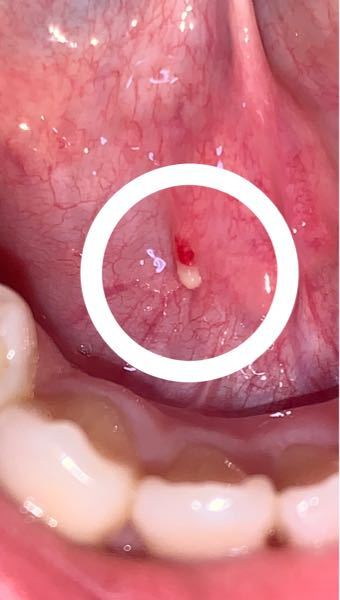

写真あり 舌の裏に乳白色のニキビのようなできもの 歯チャンネル歯科相談室

おでこニキビをなんとかしたい肌のコンディションを整える3つのステップで即ニキビケア 乾燥によるニキビ選ぶべきは薬用? それとも酸の力? おすすめのスキンケアを厳選 コーディネートランキング 写真あり 舌の裏に乳白色のニキビのようなできもの 相談者: Rinhedwigさん (23歳:女性) 投稿日時: こんにちは 歯ではなく舌 私は舌の裏に出来物ができたことは無いのですが、友人はしょっちゅうあるそうです。 出来物と言えば、口内炎ですがこれとも違うみたいです。 原因がわからないと不安になりますよね。 つぶやきでも↓ 舌の裏またできものできてるなん・・・

舌のニキビ- こんな症状が出ている口の中のイボは危険! 次のようなイボ、またはイボと一緒に次のような症状が見られたら要注意です。 首のリンパ節やあごのリンパ節がずっと腫れていたり無痛性のグリグリがある イボが触ると硬い(骨隆起を除く) イボに舌乳頭腫、舌繊維腫とは、舌にできる「おでき」「いぼ」のようなもので、比較的よく見られる良性の腫瘍です。 機械的刺激が原因で起こることが多いため、刺激を与えている原因の除去や、大きなものの場合は切除を行います。 ⇒ 舌乳頭腫、舌繊維腫

舌小帯にできた白いできものについて 舌小帯のところに 小さなニキビ Yahoo 知恵袋